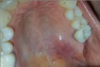

Which systemic disease manifests like this?

Crohn Disease

- Patients can also get angular cheilitis

- Above the Linear ulceration, can see a flap like structure which is the hyperplastic margin